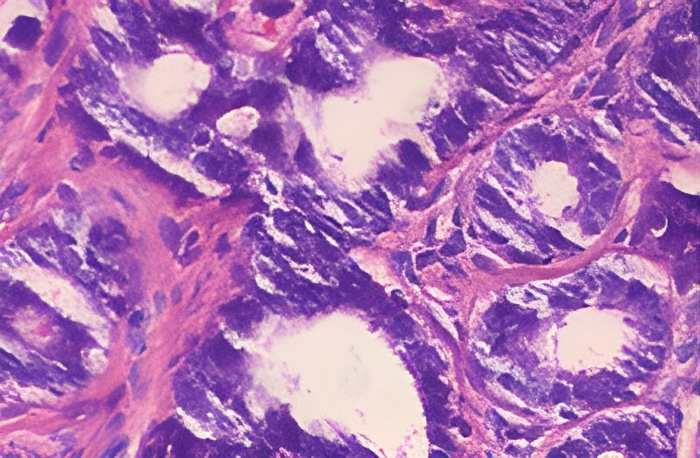

Contains the LR, HR and Fine-tuned Images with evaluation scores i.e MSE and PSNR values.